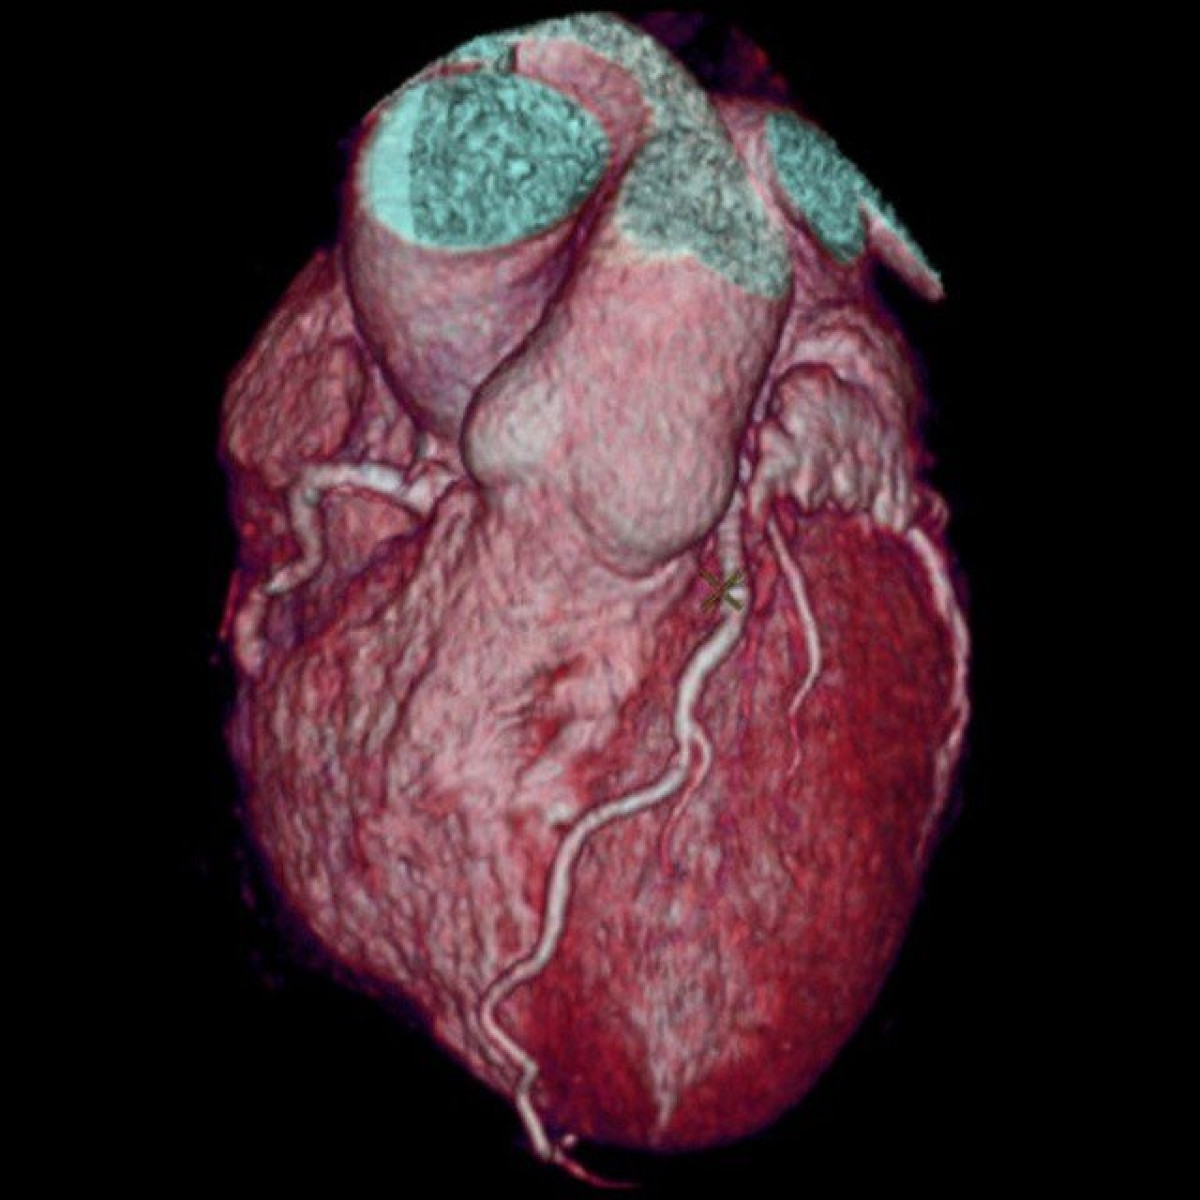

Οι υπολογιστικοί τομογράφοι ακτίνων Χ υφίστανται τα τελευταία 40 χρόνια, όμως ακόμα και σήμερα για να εξασφαλίζεται η ευκρίνεια των ακτινογραφιών ο ασθενής οφείλει να παραμένει τελείως ακίνητος κατά τη λήψη της.

Την επανάσταση έρχεται να φέρει τώρα η GE με την ανάπτυξη του νέου υπολογιστικού τομογράφου Revolution CT ο οποίος καταγράφει εύκολα και κυρίως πάρα πολύ γρήγορα μη-συνεργάσιμα μέχρι τώρα όργανα (όπως για παράδειγμα η καρδιά) κάνοντας χρήση κάμερας πολύ υψηλής ανάλησης και σύστημα σταθεροποίησης παρόμοιο με αυτό των φωτογραφικών μηχανών. Το τελικό αποτέλεσμα είναι εξαιρετικά ακριβές και ευκρινές ακόμα και στις πιο δύσκολες περιπτώσεις ασθενών.

Το επαναστατικό μηχάνημα παρουσιάστηκε στο 99ο ετήσιο συνέδριο Radiological Association of North America (RSNA) και πολύ σύντομα θα ξεκινήσει να φιλοξενείται στα νοσοκομεία των ΗΠΑ.